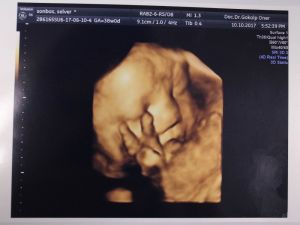

Anne karnındaki fotoğrafları 22'nci haftadan itibaren aldıklarını söyleyen Doç. Dr. Gökalp Öner, "Dört boyutlu olarak anne karnındaki bebeklerimizin yüzünü, ellerini, ayaklarını görüntüleyebiliyoruz. Bunlar aileye mutluluk veriyor. Anne ve babanın bebeğin iyi olduğunu, nasıl olduğunu görmelerini sağlıyor hem de bağlılık duygusunu sağlıyor. Anne adaylarının bebeği canlı canlı görmesi bebeklerine bağlanmasını daha çok artırıyor. Bebekleri ile çok bağ kuramayan babalar, çocuklarını gördükleri zaman daha çok bağlanıyorlar. Onların güvende olduklarını gördüklerinde de rahatlıyorlar ve mutluluk duyuyorlar. Bu dört boyutlu ultrason resimlerimiz, hem bize hem aileye mutluluk ve güven veriyor" diye konuştu.

Fotoğraflar hamilelik sürecinde mutluluk kaynağı